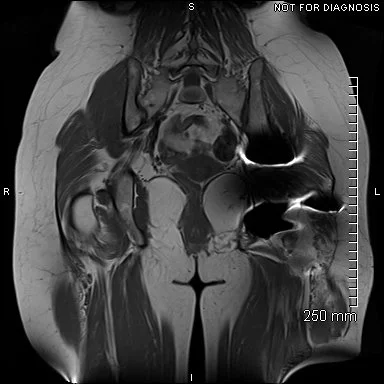

Coronal MRI showing left sided gluteal muscle wasting but no signs of loosening. There were no other abnormalities.